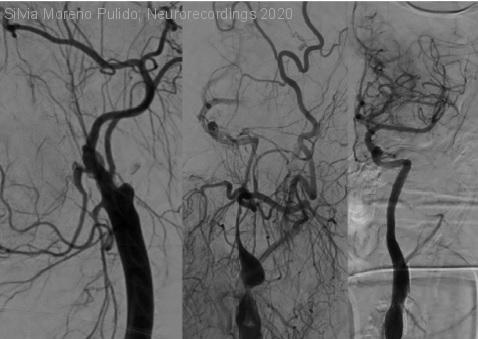

Mujer | 47 años

Diagnóstico final: Ictus isquémico tipo TACI hemisférico izquierdo de etiología inhabitual por disección espontánea de la arteria carótida interna izquierda

Mujer de 47 años, fumadora, que sufre desde hace 1 hora y 40 minutos un trastorno brusco del lenguaje y hemiplejia derecha. En la exploración neurológica objetivamos una puntuación en la escala NIHSS de 22. El...